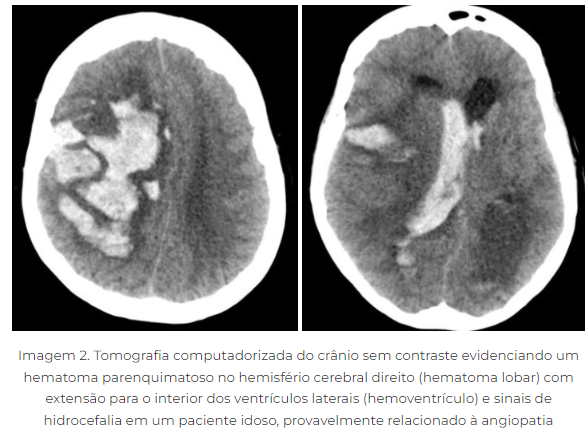

AVEh

- Hemorragia intraparenquimatosa (espontânea)

A

• principal causa HAS

• artérias perfurantes sofrem degradação aneurismatica (Charcot- Bouchard) → Rompem durante um pico hipertensivo

• locais- putamen, talamo, cerebelo e ponte

• hemorragia subcortical = angiopatia ameloide

• outras causas: transformação hemorrágico do AVCi, TCE, Ruptura de MAV

• principal problema= hipertensão intracraniana (risco de hierniação -> efeito de massa + edema vasogênico = deficit focal+ cefaleia+ Rebaixamento progressivo do nível de consciência

• putamen= hemiplegia

• Tálamo- desvio do Olhar para baixo e para dentro

• cerebelo = compressão do 4 ventrículo= hidrocefalia aguda- COMA

• Ponte= tetraplegia, coma, pupilas puntiformes, mioticas e fotorreagentes